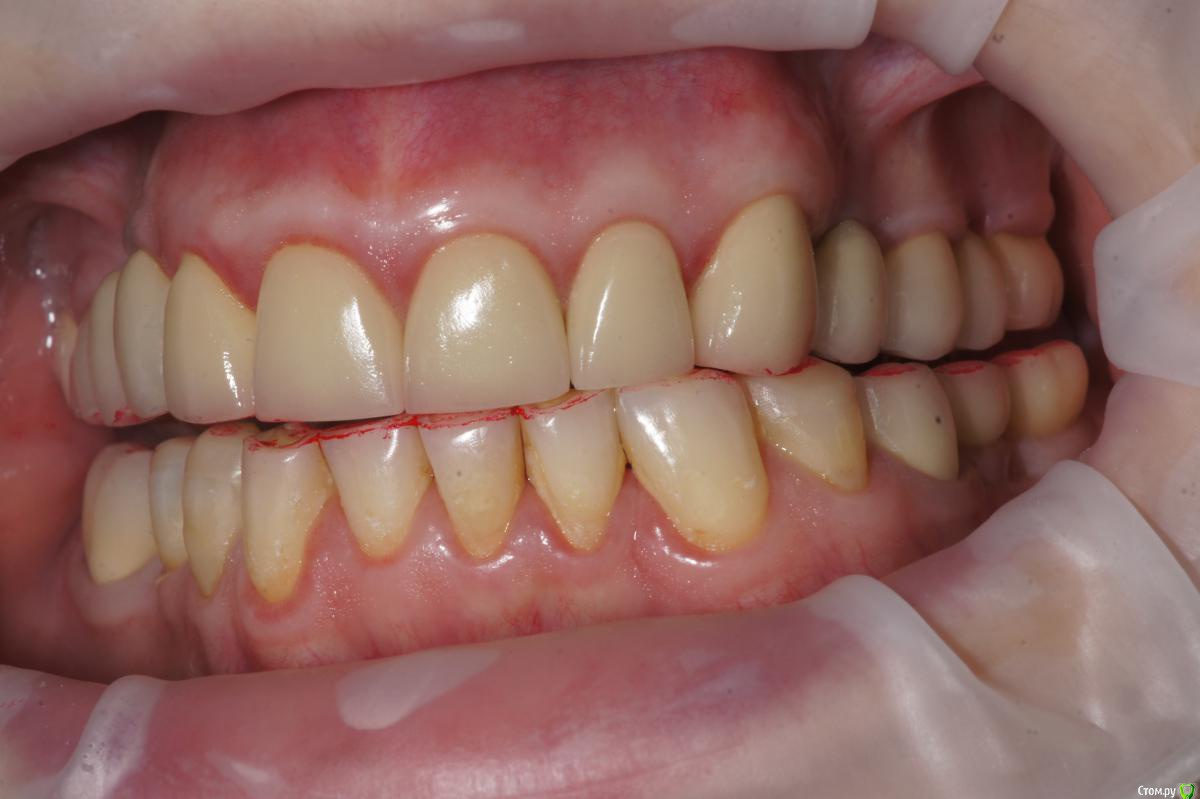

Alexandr_doc Опубликовано 21 сентября, 2018 Поделиться Опубликовано 21 сентября, 2018 Доброго всем времени! Пациентку протезировал доктор, которого уволили по ряду причин, обратилась ко мне на этапе после протезирования с жалобами на болезненность в области фронтальной группы зубов 1.2, 1.1, 2.1, 2.2, 2.3 при дотрагивании языком или пальцем. Перкуссия положительная как в вертикальном так и горизонтальном направлении. Установлены одиночные керамические коронки на каркасе из диоксида циркона. Отек, покраснение в области переходной складки отсутствует, также отсутствует болезненность при пальпации. Подвижность 1 степени. Прилагаю фотографии на этапе обращения. Ранее, на этапе протезирования было принято решение о депульпировании фронтальной группы тк присутствовала пульпитная симптоматика, после чего состояние улучшилось и остается стабильным по сей день. Предположил несколько причин оставшейся симптоматики: 1) несостоятельно проведенное эндо лечение - вариант отмел тк по прицельным снимкам и кт отсутсвуют очаги воспалительных процессов 2) некорректно изготовленные искуственные коронки ( глубокая поддесневая препаровка и агрессивный контур коронки ) 3) - окклюзионная перегрузка. Совместно с пацинеткой принято решение о снятии коронок во фронтальном отделе, была предупреждена о том, что возможно не получить хорошей динамики. С переменным успехом картина после нескольких корректировок временных коронок остается преждней. Болезненность на прежднем уровне, плюс по ходу наблюдения пришлось снять мост с опорой на уровне имплантатов, тк имели место быть воспалительные процессы в проекции имплантата 1.5. С удовольствием отвечу на все вопросы и приму любую критику. Ссылка на комментарий

Дмитрий Л. Опубликовано 21 сентября, 2018 Поделиться Опубликовано 21 сентября, 2018 Маргинальной гингивит. Нависающие края? Мягкий налет под коронками? Остатки цемента? Скоро будет пародонтит. Ссылка на комментарий

Alexandr_doc Опубликовано 21 сентября, 2018 Автор Поделиться Опубликовано 21 сентября, 2018 Точно ли на кт нет изменений на корнях зубов? Мне на рентгеновских снимках что-то видится. жесткая каппа на верхний зубной ряд - я бы начал с этого.Нижние резцы устойчивы?Чем вам не нравится глубокая поддесневая препаровка? Десна выглядит также как и на интактных зубах НЧ.Как проверяется работа на предмет локальной перегрузки - не знаю, расскажите пожалуйста.На кт изменений нет, мне хотелось их найти, но нет. Мне будет не сложно сделать срезы и приложить их к посту, рассматривал некачественное эндо как один из первых причинных факторов. Жесткая капа какая? Какой дизайн и схему порекомендуете? Десна действительно сейчас выглядит также как и в других участках. При гипсовке в ЦС проверены: наличие первого контакта на фронтальной группе, проверена схема направляющих, распределение контактов на моделях. Ссылка на комментарий